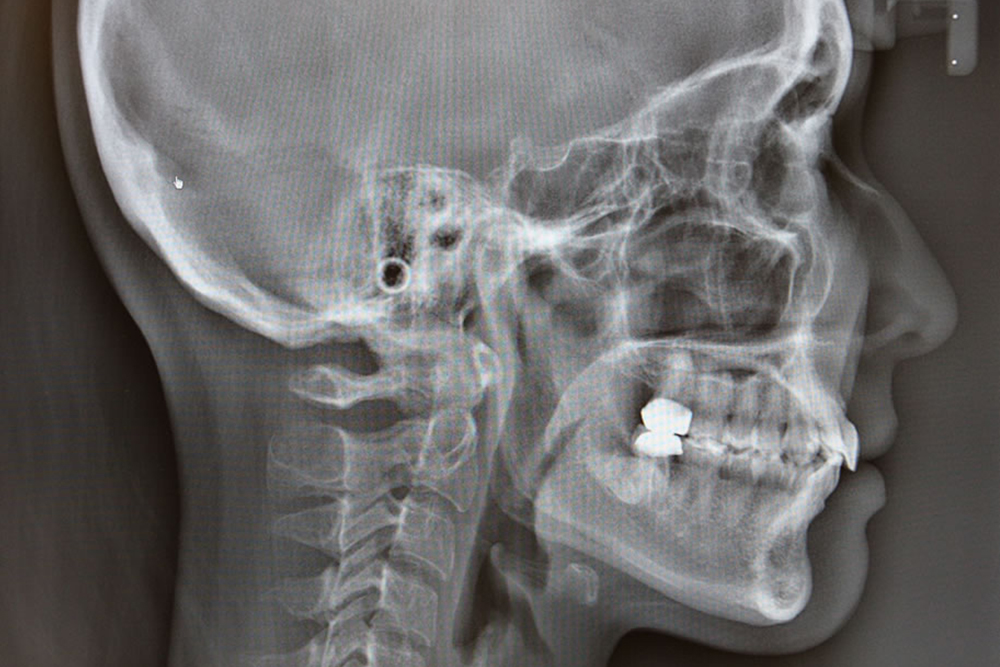

セファロレントゲン

頭部から顎までのX線画像を撮影できる装置です。矯正治療の診断や顎のバランス、治療経過の確認などに使用します。